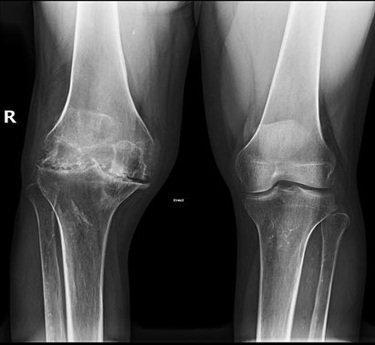

Haemophilic arthropathy

Haemophilia is a disease characterized by inability of the blood to clot. This can lead to recurrent bleeding. Recurrent bleeding into the joints can lead to arthropathy. Treatment would require correction of the clotting abnormalities often using clotting factors.